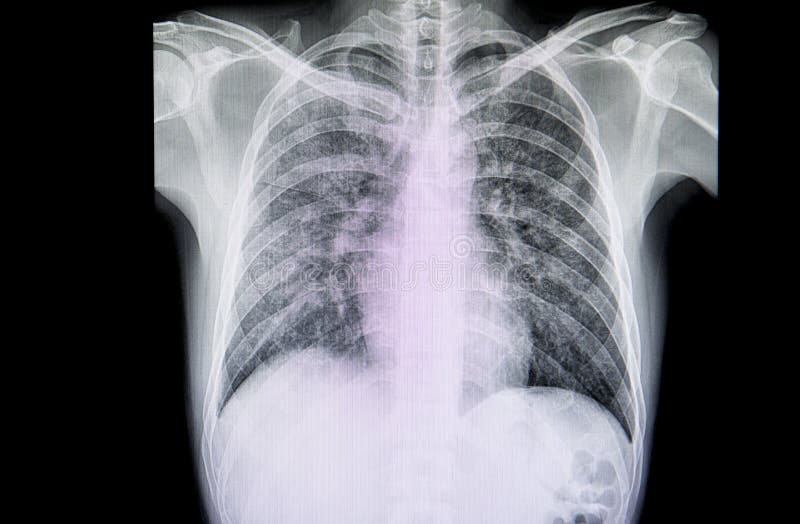

Trauma toracico con fratture costali multiple ( 9 e 10) a dx con obliterazione del seno costofrenico da versamento pleurico di lieve entità. Trova le valutazioni dei pazienti, i servizi offerti dal dottore e verifica la prima data disponibile. Versamento pleurico, tuttavia alcuni versamenti pleurici sono per lo più asintomatici e vengono.

Sintomi di versamento pleurico sfortunatamente, segni clinici di versamento pleuricopuò essere molto sottile, quindi è importante essere consapevoli dei sintomi che indicano che il tuo cane o gatto ha difficoltà a respirare. .costola e versamento pleurico ed enfisema sottocutaneo fratture multiple della costola e hemothorax sinistro un esame radiografico del torace di un paziente con le fratture della costola e versamento pleurico ed enfisema sottocutaneo cardiomegalia e fratture multiple delle costole film. La frattura alle costole avviene per un trauma diretto, che può essere determinato dallo schiacciamento o dallo sfondamento. Non sono mancate, nel corso degli anni, le privazioni e le umiliazioni subite dalla madre, che in un'occasione era stata cosparsa di acqua e shampoo e buttata fuori di casa. Il versamento pleurico è un accumulo di liquido in eccesso nella cavità pleurica che se non trattato può portare a conseguenze serie. Il versamento pleurico e' abbastanza frequente in caso di fratture costali multiple, potrebbe esserci anche un pneumotorace, quindi il drenaggio in questo caso va mantenuto, e anche una copertura antibiotica per evitare pleuriti, se non c'e' sangue ma liquido giallino e' un buon segno. Trauma toracico con fratture costali multiple ( 9 e 10) a dx con obliterazione del seno costofrenico da versamento pleurico di lieve entità. Il versamento pleurico può portare a mancanza di respiro che peggiora progressivamente e, quando non dovesse riassorbirsi spontaneamente, potrebbe essere necessario drenare direttamente. Le costole solitamente possono rompersi o fratturarsi a causa di un colpo diretto al torace o al busto, come in un incidente stradale, per una brutta caduta o per è importante rivolgersi a un medico dopo una frattura di un certo rilievo, perché se l'osso si frantuma (diversamente da quanto accade per una. • versamento trasudato • versamento essudato • emotorace • empiema versamento pleurico essudato. Dopo una serie di esami fatti, dalle lastre sono risultate alcune costole fratturate e un conseguente versamento polmonare. Il termine versamento pleurico, estratto dal linguaggio medico, rimanda ad un eccessivo accumulo di liquido all'interno della cavità pleurica. La frattura alle costole comporta, come sintomo più evidente, il dolore. Indagine di primo livello che può svelare la causa di una pleurite in una polmonite, frattura costale o tumore del polmone. Liquido si forma sul versante parietale e liquido si riassorbe sul versante viscerale. Sintomi di versamento pleurico sfortunatamente, segni clinici di versamento pleuricopuò essere molto sottile, quindi è importante essere consapevoli dei sintomi che indicano che il tuo cane o gatto ha difficoltà a respirare. I medici tratteranno il disturbo responsabile del versamento pleurico ed eseguiranno un drenaggio del liquido tramite un l'ago o la cannula vengono inseriti attraverso la parte laterale del torace, tra due costole.